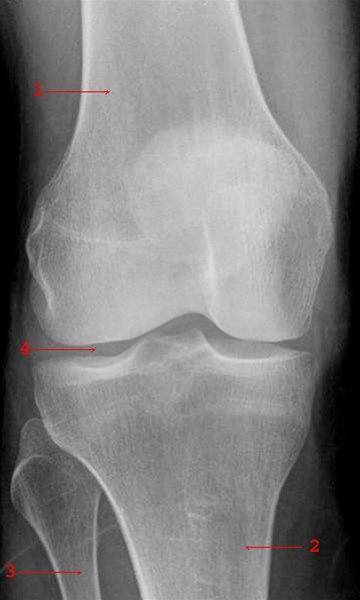

Røntgenbilde av kne - forfraDette er en tilstand som skyldes infeksjon med bakterier i ett, eller i enkelte tilfeller noen få ledd. Tilstanden kalles på fagspråket bakteriell - ev. septisk - artritt. Det er som regel store ledd, som for eksempel hofte-, kne- eller skulderledd, som blir rammet. Bakteriene kommer vanligvis fra et sår eller en underliggende infeksjonssykdom, og bakteriene sprer seg til leddet oftest via blodet.